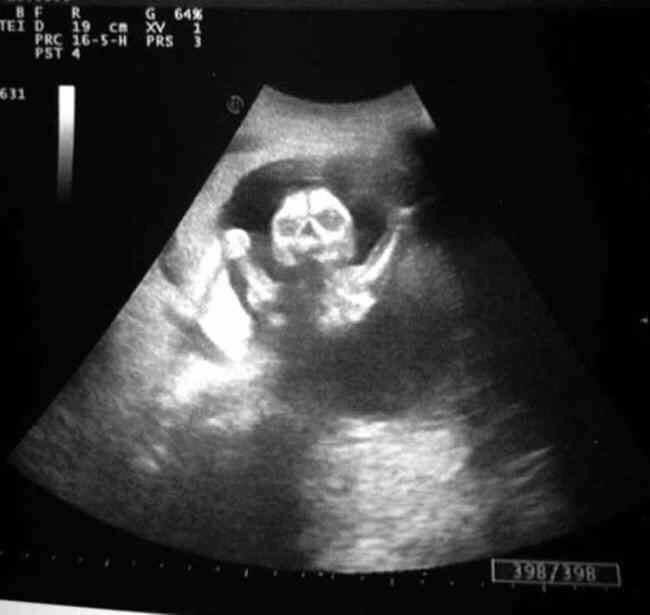

Made a quick gif showing fracture healing. Acute, 10d, 1mo, 2mo, 3mo, 6mo intervals. #radiology #FOAMed #fracture Radiopaedia.org